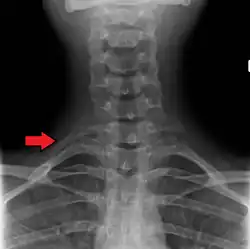

Variations in the number of ribs occur. About 1 in 200–500 people have an additional cervical rib, and there is a female predominance.[13] Intrathoracic supernumerary ribs are extremely rare.[14] The rib remnant of the 7th cervical vertebra on one or both sides is occasionally replaced by a free extra rib called a cervical rib, which can mechanically interfere with the nerves (brachial plexus) going to the arm.

X-ray image of a human chest, with ribs labelled -